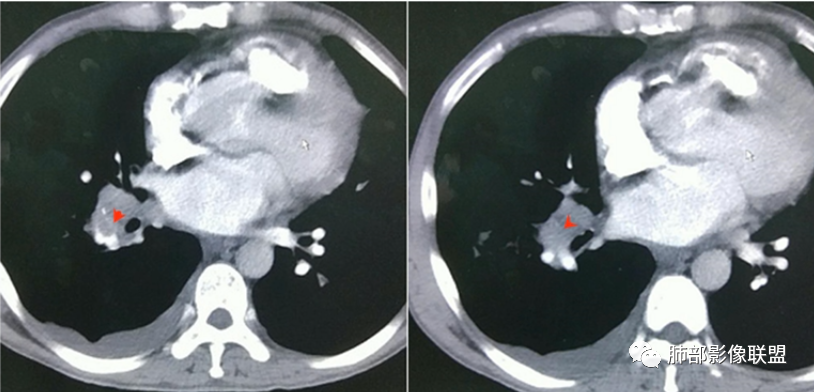

早期脓毒栓子可以,楔形。

内部低密度影都符合

这些是典型的 |

2.影像上肺多发混合密度片影,随机分布,胸膜下分布优势,病灶边界大多隐约可辨,偏柔和,动脉血管影穿行,未见钙化、液化空洞、或明确气囊影,未见树芽征。

1.外围分布,胸膜下为主,两肺弥漫结节或胸膜下楔形影,边界清,周围伴有GGO

2.反晕征:往往紧贴胸膜,并且胸膜侧无环,周围GGO

7.增强可见肺动脉栓子(少见)